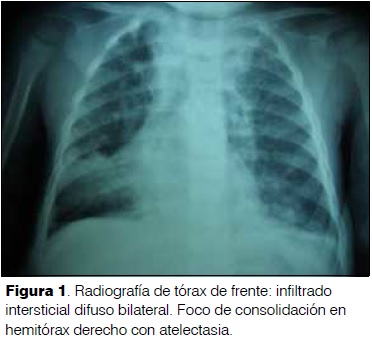

Un año y un mes. Sexo masculino. Medio socioeconómico deficitario. Mal inmunizado. Buen desarrollo. Disalimentado. Desnutrición crónica. Bronquiolitis aguda a los 6 meses. Neumonía aguda izquierda a los 8 meses. Presentó tos catarral de 3 días de evolución, rinorrea serosa, agrega dificultad respiratoria, fiebre de 38ºC axilar, y rechazo del alimento. Al examen: Reactivo. Palidez cutáneo mucosa. Frecuencia respiratoria 56 rpm. Saturación de O2 ventilando al aire 98%. No tirajes. Murmullo alvéolo vesicular presente bilateral. Foco de estertores crepitantes en cara lateral y posterior de hemitórax derecho. Hemograma: glóbulos blancos 13.100 elementos/mm3, neutrófilos 44%, hemoglobina 10,2 g/dl, plaquetas 448.000 elementos/mm3. Proteína C reactiva 96 mg/l. Radiografía de tórax: Infiltrado difuso bilateral. Foco de consolidación en lóbulo medio hemitórax derecho con atelectasia (figura 1). Se plantea neumonía aguda derecha y se inicia ampicilina intravenosa con buena evolución inicial. A las 48 h persiste febril, instala dificultad respiratoria. Saturación de O2 ventilando al aire 93%. Abundantes estertores subcrepitantes difusos bilaterales. Familiar refiere episodio de sofocación mientras comía maní horas antes del inicio de la enfermedad actual. Se rota antibiótico a ampicilina–sulbactam intravenosa. Mediante broncoscopía rígida se extraen fragmentos de maní. Buena evolución clínica.

80,3% de los pacientes presentaron elementos patológicos en la radiografía de tórax, siendo 19,7% normales(10). Los cuerpos extraños orgánicos son radiolúcidos, por lo cual es útil buscar signos indirectos en la radiografía: atelectasia (41%); neumonía (32,4%); atrapamiento aéreo o enfisema obstructivo (23%); desviación mediastinal, neumomediastino, y neumotórax son menos frecuentes(3,12,14). Los elementos radiológicos presentes en esta serie de casos fueron: neumonía, atelectasia, desviación mediastinal, y atrapamiento aéreo.